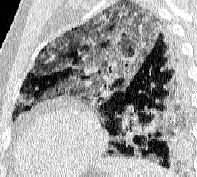

Lung segmentation results for the polymorphic and nonpolymorphic models are shown in Figure 3. Quantitative evaluation of lung segmentations was performed on CT images by comparing the segmentations to ground truth manual segmentations. The Dice coefficient was used to measure volume overlap and the average symmetric surface distance (ASSD) was used to assess boundary accuracy. The ASSD and Dice coefficient results for each of the four evaluation datasets are shown in Table 2. Overall, on the COVID-19 dataset the polymorphic model achieved an average ASSD of mm and average Dice coefficient of . By comparison, the nonpolymorphic model achieved an average ASSD of mm and average Dice coefficient of . ASSD and Dice coefficient results with respect to nonaerated lung volume fraction are displayed in Figure 4. Two-way analysis of variance revealed a significant interaction between model and nonaerated fraction for each evaluation metric, indicating that the regression coefficients with respect to nonaerated fraction were significantly different for polymorphic vs. nonpolymorphic models.

Lobar Segmentation

Lobar segmentation results for the proposed method and PTK are shown in Figure 5 for right lungs and Figure 6 for left lungs. For each image in the COVID-19 dataset (133 images in total), the lobar segmentation result was used to extract the amount of poor aeration () and consolidation () in each lobe. Common phenotypes of COVID-19 affected lungs were identified by hierarchical clustering over the fraction of poorly aerated and consolidated tissue in each lobe. Dendrographic analysis in Figure 7 reveals four primary clusters of patients that were identified by the hierarchical clustering: (a) mild loss of aeration primarily in the two lower lobes without consolidation; (b) moderate loss of aeration focused in the two lower lobes with or without consolidation in lower lobes; (c) severe loss of aeration throughout all lobes with or without consolidation; and (d) severe loss of aeration and consolidation throughout all lobes.